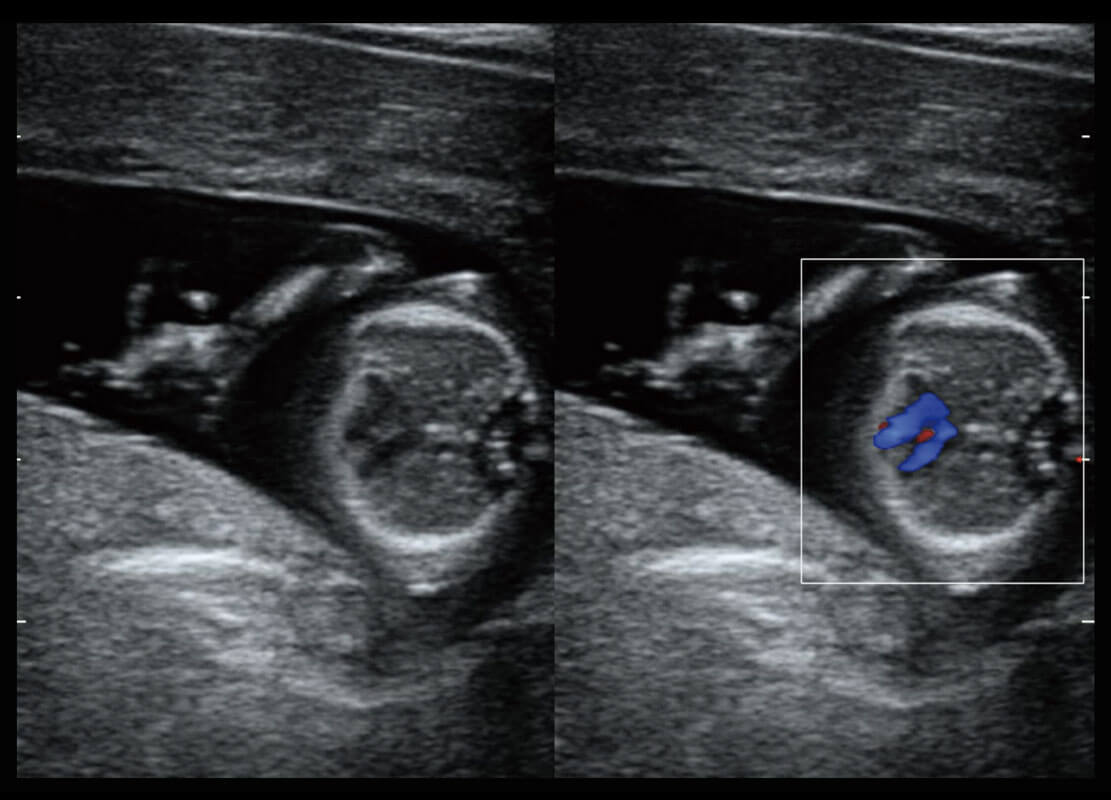

早孕-胎心

P60在胎儿早孕期超声筛查中为您带来优异的图像质量。